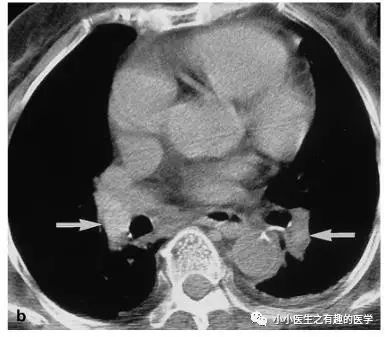

翠花上菜,学者上图。

发现嫌疑犯,立即逮捕。

增强CT对比,一目了然。